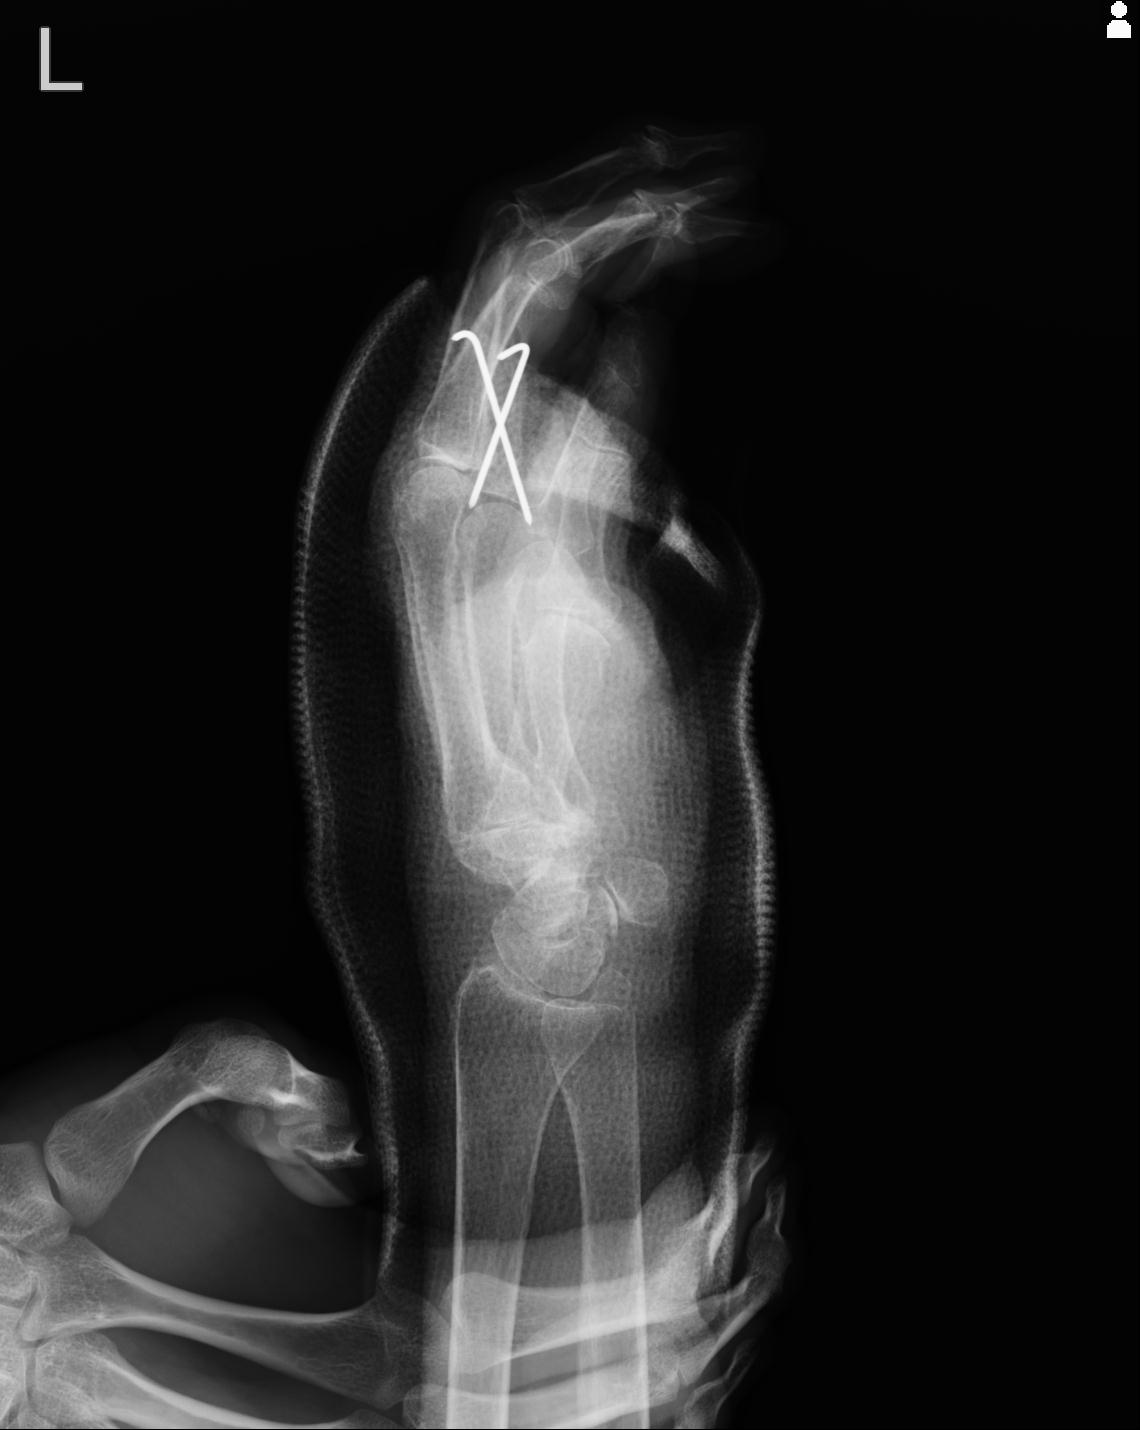

20857 1/11 左手 3R 1/19 4R 55歳男性 小指中節骨骨折